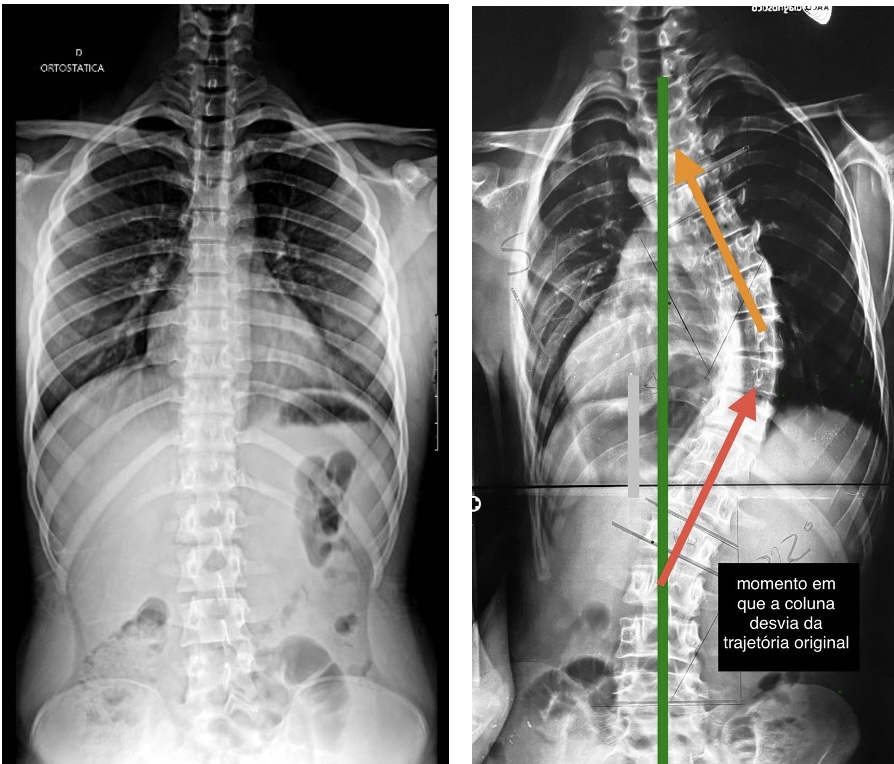

Escoliose, por definição, é um desvio da coluna vertebral em três planos:

- quando observada de frente ou de costas (plano coronal),

- quando observada de lado (plano sagital),

- e no próprio eixo da coluna, com rotação das vértebras.

Além disso, para que esse desvio seja considerado escoliose, ele precisa ultrapassar 10 graus, medidos no raio-x por uma medida chamada ângulo de Cobb.

Uma forma simples de entender esse conceito é imaginar uma linha que deveria seguir reta em direção a um ponto. Em determinado momento, essa linha faz uma curva e modifica sua trajetória. É isso que acontece com a coluna na escoliose.